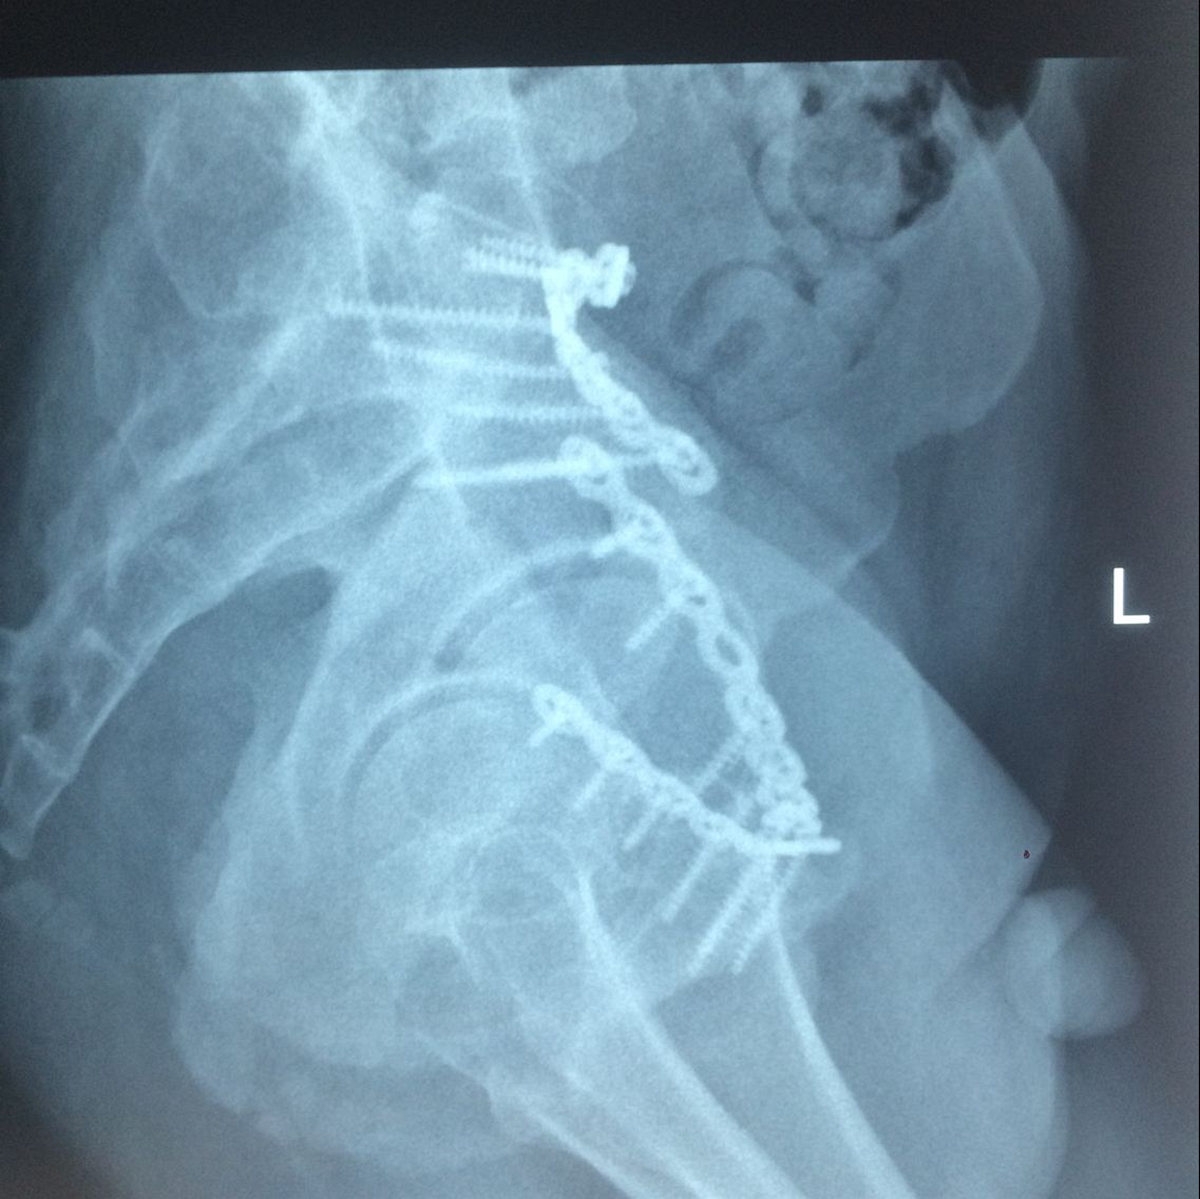

患者术后复查X片情况

术后X片